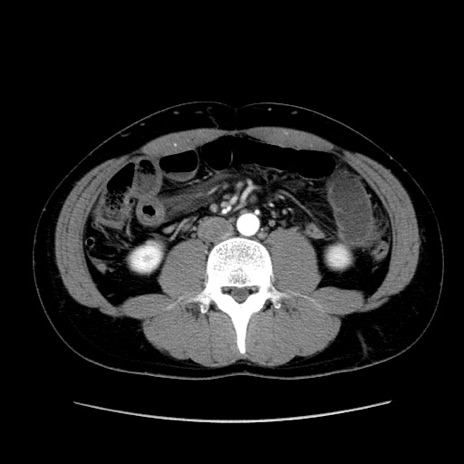

症例36(横断像)

【症例】20歳代 男性

【主訴】心窩部痛

【現病歴】今朝より上腹部痛あり。一旦軽快していたが再度出現したため救急要請。昨日夕に白身の魚を含む刺身を食べた。

【身体所見】BP 136/89mmHg、HR 74/min、BT 37.0℃、腹部:膨満、軟、心窩部に圧痛あり。反跳痛なし、筋性防御なし、腸雑音やや亢進あり。

【データ】WBC 17700、CRP 0.48